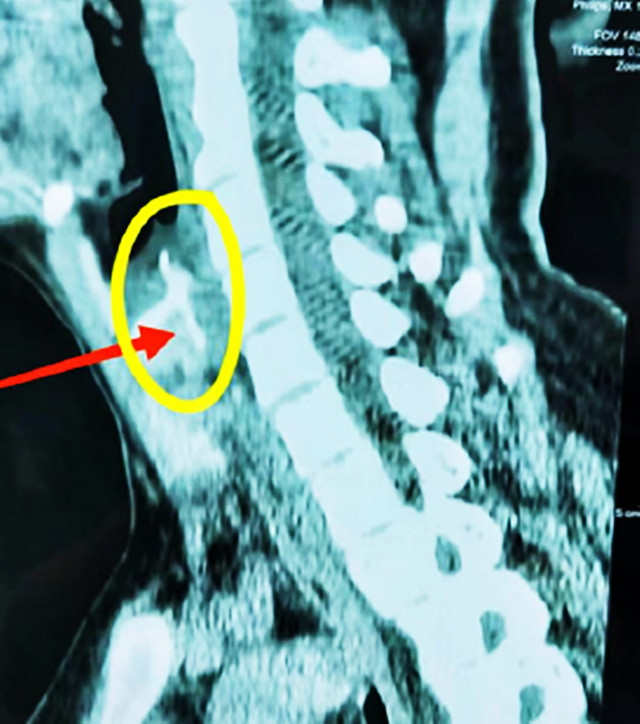

穿透食道壁。鱼刺可能穿透食道壁,进入周围的纵隔、胸腔或气管,引发纵隔炎、气胸、气管食管瘘等并发症,治疗难度大幅增加,且恢复周期长。